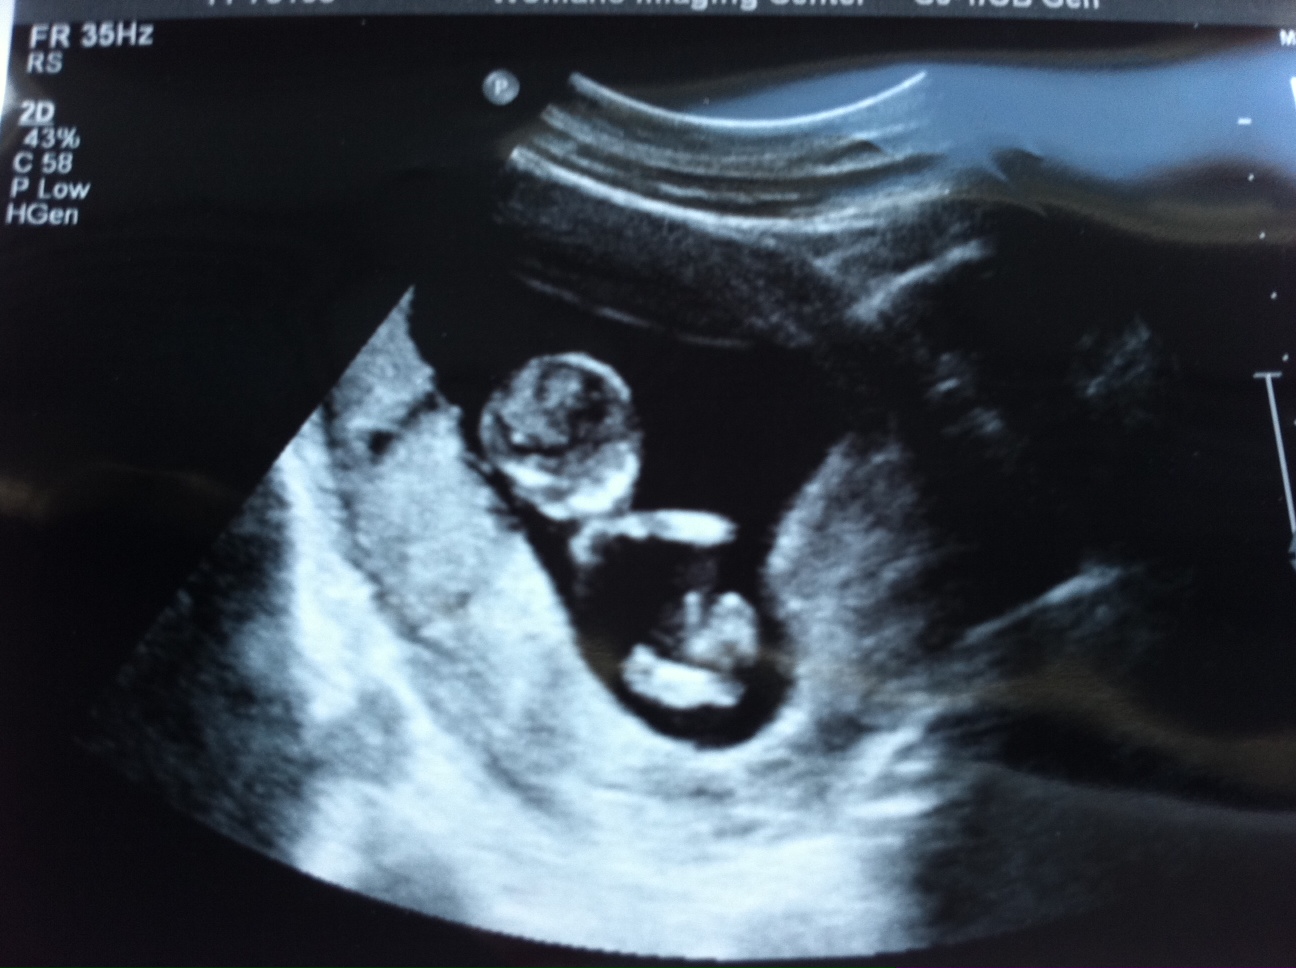

While we’re at it, here’s some photos from my 13-week ultrasound. I know some people are irritated by ultrasound pictures (I used to be one of those people until I figured out how to look at it), but y’all can suck it up for a second. Kthanks.

Yoga baby! It’s crossing its arms and legs.

I actually think you can see a little baby here! It’s facing us, and has its chin resting on its arm.

I take that back about the hermaphrodite. Maybe I am having an alien.